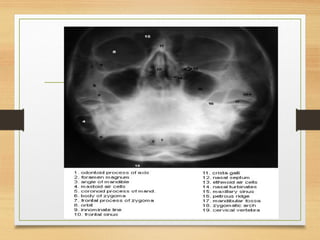

Investigations

• Submentovertex (Jughandle)---Arch fracture

• Occipitomental view - ZOM fracture

• CT Scan-------Gold standard

Investigations • Submentovertex (Jughandle)---Archfracture • Occipitomental view - ZOM fracture • CT Scan-------Gold standard